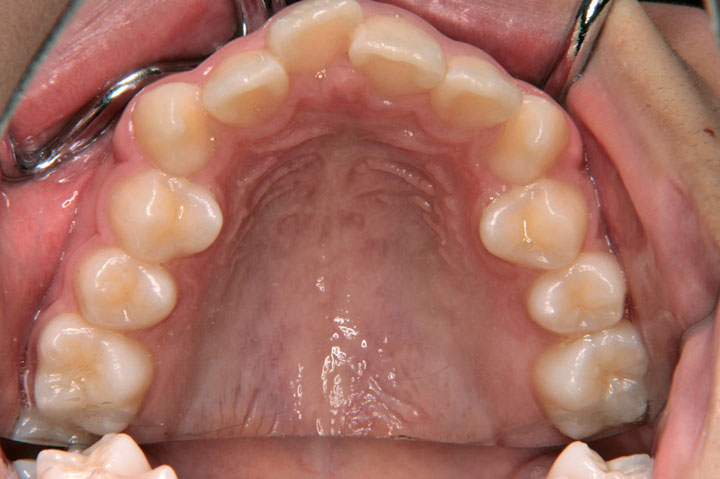

過蓋咬合(深いかみ合わせ)

叢生(乱ぐい歯)

上顎前突(出っ歯)

上顎の前突感と歯の不正を主訴に来院された中学校2年生の女子です。上顎前突、過蓋咬合、叢生などが複合する不正状態で、上顎小臼歯の抜歯をお願いしてデーモンシステムを用いたエッジワイズ治療を行いました。動的治療期間2年8ヶ月を要しましたが、装置を撤去し保定に移行しております。